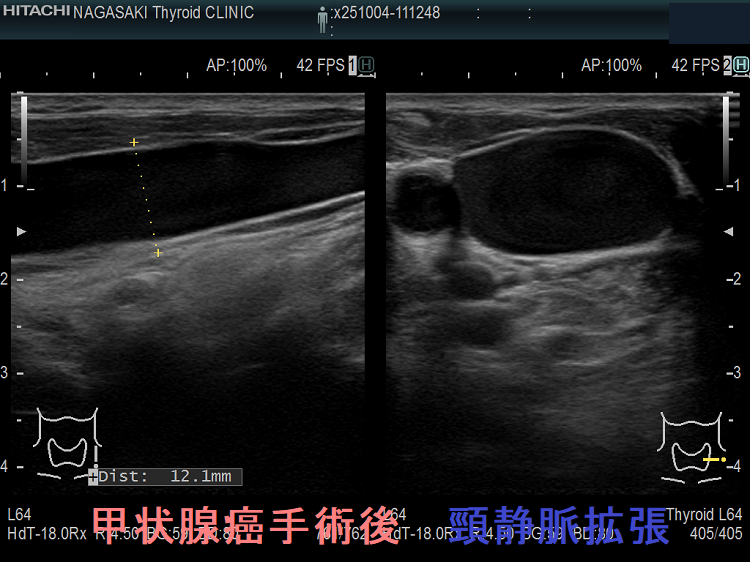

甲状腺癌術後、頸横動脈仮性動脈瘤が生じて破裂する事があります。

報告例は、頚椎後縦靱帯骨化症(OPLL)のため頸部伸展位を取れない状態で外深頸リンパ節を郭清した際、頸横動脈の外膜を傷付け仮性動脈瘤が発生したと推察されます。甲状腺癌手術を終え退院後13日目に頸部痛と左肩甲部から前頸部にかけて腫瘤形成が起きた。画像診断にて頸横動脈瘤とその破裂による大出血と診断し、コ イル塞栓術にて治癒したそうです。(日臨外会誌 67 (10), 2289-2293, 2006)